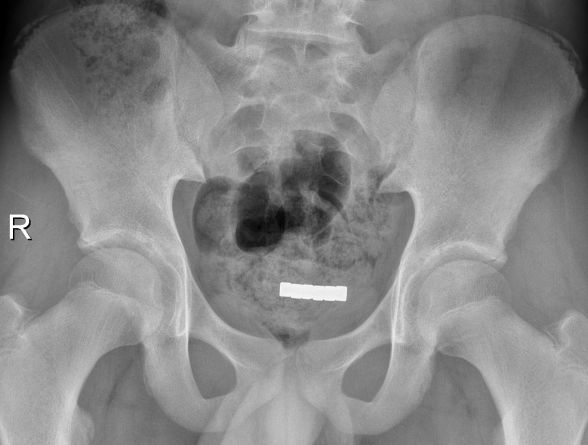

腹部X线片检查发现患者膀胱区有一个长方体形状的异物,长度约5cm,宽度约0.8cm,厚度约0.8cm,且密度很高,考虑是膀胱异物,泌尿外科迅速完善术前检查,小伙子入院后不到两个小时就躺到了手术台上。

膀胱镜下发现小伙子膀胱内竟然是六块正方体形状的磁铁,相互吸引后形成了一个长条形的“磁条”。用膀胱镜下的异物钳夹磁铁时发现,因为有磁性存在,异物钳一靠近磁铁,磁铁就吸附在异物钳边缘处,很难调整角度。泌尿外科随即更换用套石篮,但是适用于输尿管镜的套石篮开口普遍很小,无法将磁铁整个套住,一时间难住了医疗团队。